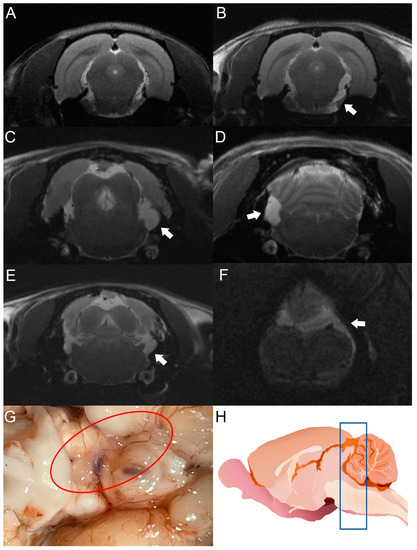

After cyst inoculation in a pilot experiment, the presence and distribution of cysts in the brain of rats were verified by MRI. Infected animals exhibited a time-dependent increase in parasite size. Cysticerci were not visible yet by MRI in one rat on day 30 post-infection (Figure 3A). However, an image compatible with a cysticercus was found in the periphery of the cisterna magna of the same rat on day 120 post-infection (Figure 3B). The other four animals analyzed showed images compatible with cysts in the basal cisterns, the cisterna magna, or in the spinal subarachnoid space. No intraparenchymal parasites were observed (Figure 3C–F). Racemose cysticerci were found on postmortem examination in the brain regions of interest on day 120 post-infection (Figure 3G,H). No clear evidence of hydrocephalus or ventricle enlargement was observed.

Figure 3. MRI studies of rats infected with T. crassiceps cysts at different times post-infection. Comparative parasite growth between day 30 (A) and day 120 (B) post-infection. (CF) Photographs showing parasite growth in extraparenchymal regions of several animals on day 120 after infection. The location of the parasites is indicated by white arrows. (G) Macroscopic appearance of racemose cysticerci on day 60 post-infection (red circle). (H) Schematic representation showing the brain region analyzed by MRI (blue box). The brains of 5 infected animals were analyzed.

The use of MRI is indispensable to detect cysticerci in extraparenchymal locations. This tool has been optimized with the FIESTA sequence, which makes it possible to discriminate the signal emitted by CSF from the cysticercus itself [40]. In our study, cysticerci were detected by MRI on day 30 post-infection, as shown in Figure 3.